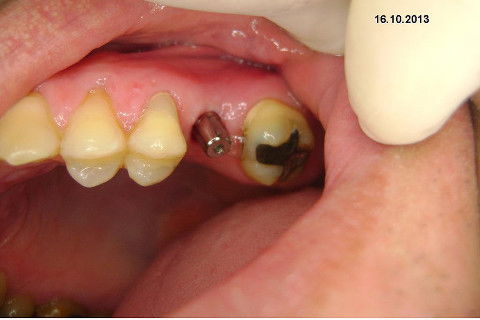

Instalação de um implante em região do 26. Utilizamos um implante cone morse Alvim Neodent 4.3 X 11,5. Foi uma cirurgia muito rápída e minimamente traumática, sem retalho e sutura.